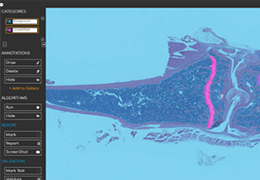

ART-Plan™ Artificial Intelligence Contouring